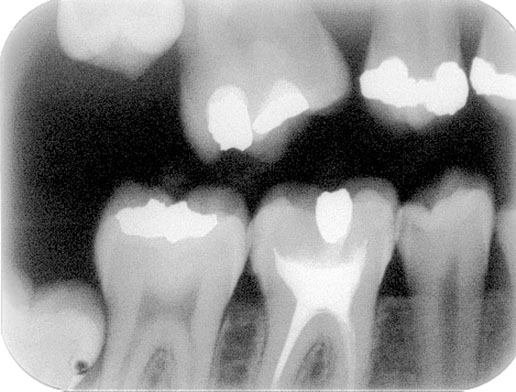

Streszczenie Zdjęcie skrzydłowo-zgryzowe pozwala na obrazowanie koron zębów oraz brzegu wyrostka zębodołowego szczęki i żuchwy. Powstaje poprzez ustawienie promienia centralnego zgodnie z przebiegiem skrzydła, które zagryza pacjent. Słowa kluczowe: radiografia, technika skrzydłowo-zgryzowa, pozycjoner Pełna wersja artykułu dostępna w prenumeracie i sieci salonów Empik (półka: prasa popularno-naukowa). Piotr Malisz, Anna Duis Zakład Elektroradiologii, Instytut Fizjoterapii, Wydział Nauk o Zdrowiu UJ…

Wprowadzenie Jedną z metod radiologicznych wykorzystywanych w diagnostyce stomatologicznej jest badanie pantomograficzne. Jest to badanie pozwalające na obrazowanie struktur zakrzywionych twarzoczaszki. Zdjęcie pantomograficzne jest obrazem warstwowym wyrostka zębodołowego szczęki i żuchwy powstającym poprzez synchroniczny obrót układu lampa rentgenowska (źródło promieniowania) – detektor promieniowania wokół głowy pacjenta. Zarówno lampa, jak i detektor są umieszczone na zewnątrz pacjenta – zdjęcia zewnątrzustne. Na fotografii 1 przedstawiono zdjęcie pantomograficzne wyrostka…